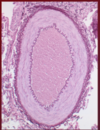

What is the structure depicted here?

Label 1-4

- Large vein (vena cava)

1) Tunica media

2) Tunica adventitia

3) Tunica intima

4) Simple squamous epithelium